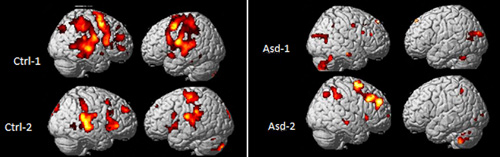

Med fMRI-undersøkelse skal vi studere hjerneforandringer som er assosiert med barnas motstand mot uforutsette endringer og dermed det nevrobiologiske grunnlaget for et slikt symptom. Hypotesen er at barn med autisme reagerer annerledes på uventede hendelser enn barn som ikke har autisme, og at dette kan ses ved et funksjonelt MR-opptak. Barna får en lytteoppgave med uventede hendelser.

Så langt har vi få pasienter. Det er for tidlig å konkludere, men det virker å være en tendens til støtte til hypotesen vår om at barn med autisme har endringer i både nevronal aktivitet ved fMRI og synaptisk aktivitet målt ved MR-spektroskopi sammenliknet med friske kontrollbarn.